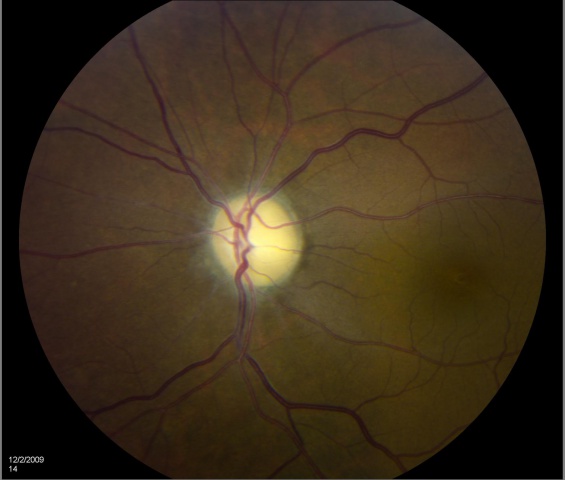

Optic atrophy is a sign and is typically noted as optic nerve pallor. This is the end stage of a process resulting in optic nerve damage. Because the optic nerve fiber layer is thinned or absent, the disc margins appear sharp and the disc is pale, probably reflecting absence of small vessels in the disc head.

EXAMPLES OF OPTIC ATROPHY (NEUROPATHY):

Optic atrophy refers to the death of the retinal ganglion cell axons that comprise the optic nerve, and manifests on fundoscopy as a pale optic nerve. Optic atrophy is the end stage of myriad causes of optic nerve damage anywhere along the path from the retina to the lateral geniculate. Since the optic nerve transmits retinal information to the brain, optic atrophy is associated with vision loss. However, the term "atrophy" is somewhat of a misnomer as it implies disuse; thus, this optic nerve damage is better termed "optic neuropathy."

Certain disc appearances can help to determine the cause of the optic nerve damage. Sector disc pallor in an older individual could have been caused by nonarteritic ischemic optic neuropathy. Severe optic atrophy with gliosis could have been due to giant cell arteritis. Damage from papilledema may leave retinal folds and sometimes glistening bodies in the optic nerve head. Cupping is suggestive of glaucoma.